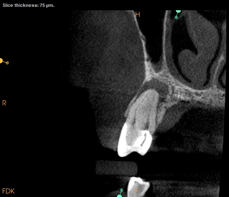

Lastly, regardless of the treatment approach pursued, it is essential to tend to the psychological needs of the patient experiencing a flare-up. The patient should be reassured that the condition is treatable and that flare-ups are quite distinct from treatment failure. In fact, their occurrence has not been shown to affect the overall prognosis of NSRCT (Figure 2 through Figure 5).39,40 Because significant preoperative pain complaints have been associated with a greater risk of flare-up, these patients should be counseled and duly warned of the possible occurrence of a flare-up. Simple discussions on pain management and after-hours emergency availability can significantly reduce the stress of flare-ups for providers and patients alike.14

Fig 2. Case demonstrating successful healing of tooth No. 5 following a flare-up incident. Fig 2: Patient presented with asymptomatic apical periodontitis of tooth No. 5. Fig 3: Following initiation of NSRCT, the patient developed a flare-up with swelling and pain. Amoxicillin was prescribed and the calcium hydroxide medicament was replaced. Fig 4: The patient returned 3 months later with radiographic healing of the apical periodontium. Fig 5: Obturation was completed.

Fig 4. Case demonstrating successful healing of tooth No. 5 following a flare-up incident. Fig 2: Patient presented with asymptomatic apical periodontitis of tooth No. 5. Fig 3: Following initiation of NSRCT, the patient developed a flare-up with swelling and pain. Amoxicillin was prescribed and the calcium hydroxide medicament was replaced. Fig 4: The patient returned 3 months later with radiographic healing of the apical periodontium. Fig 5: Obturation was completed.

Figure 4

Fig 5. Case demonstrating successful healing of tooth No. 5 following a flare-up incident. Fig 2: Patient presented with asymptomatic apical periodontitis of tooth No. 5. Fig 3: Following initiation of NSRCT, the patient developed a flare-up with swelling and pain. Amoxicillin was prescribed and the calcium hydroxide medicament was replaced. Fig 4: The patient returned 3 months later with radiographic healing of the apical periodontium. Fig 5: Obturation was completed.

Figure 5